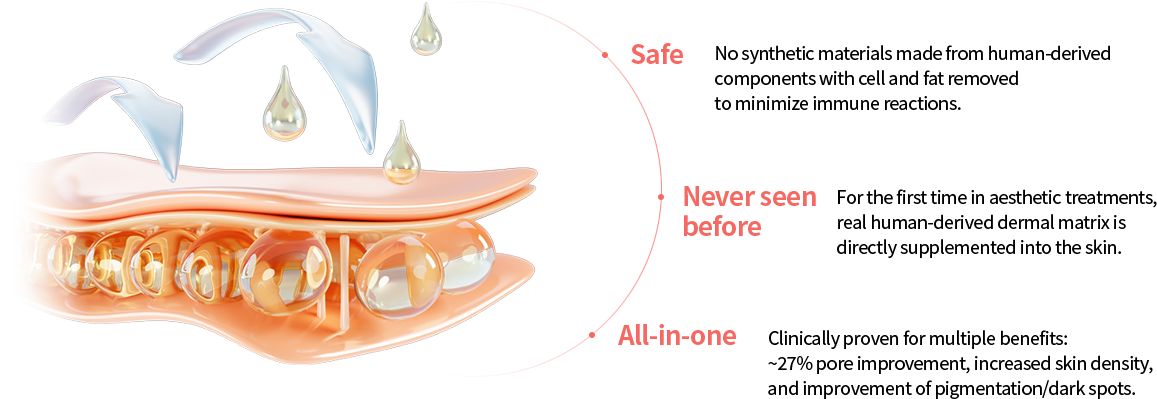

70% of Collagen Structure

Glycine, proline, and lysine account for approximately 70%

of the collagen structure. During fibroblast metabolic activity,

these amino acids stimulate fibroblasts to promote collagen

production and support collagen synthesis, helping improve

skin firmness and structural integrity.